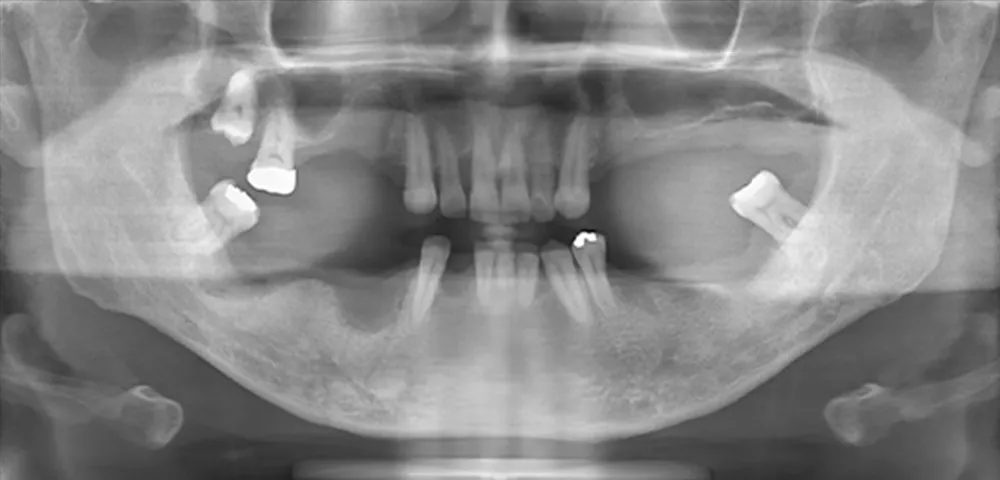

さまざまなトラブルやリスクを伴うインプラント治療には、患者様一人ひとりの骨や健康状態に応じた専門的な診断と高精度な技術が求められます。国内外で研鑽を積む理事長が、より安全で精密な治療をお届けします。骨が少ない、持病があるなど、一般の歯科医院では対応が難しい方も一度ご相談ください。

通算911本の(※2024実績)

インプラント埋入実績 -